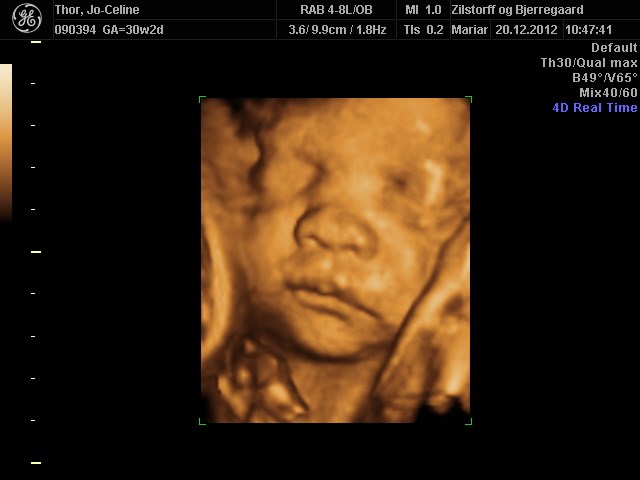

Søger man på Google kommer der kun 3D-billeder.

Så jeg vil høre om nogen herinde har et billede eller to fra uge 28 de vil vise? Og hvor lang var jeres baby, og fik I vægt at vide?